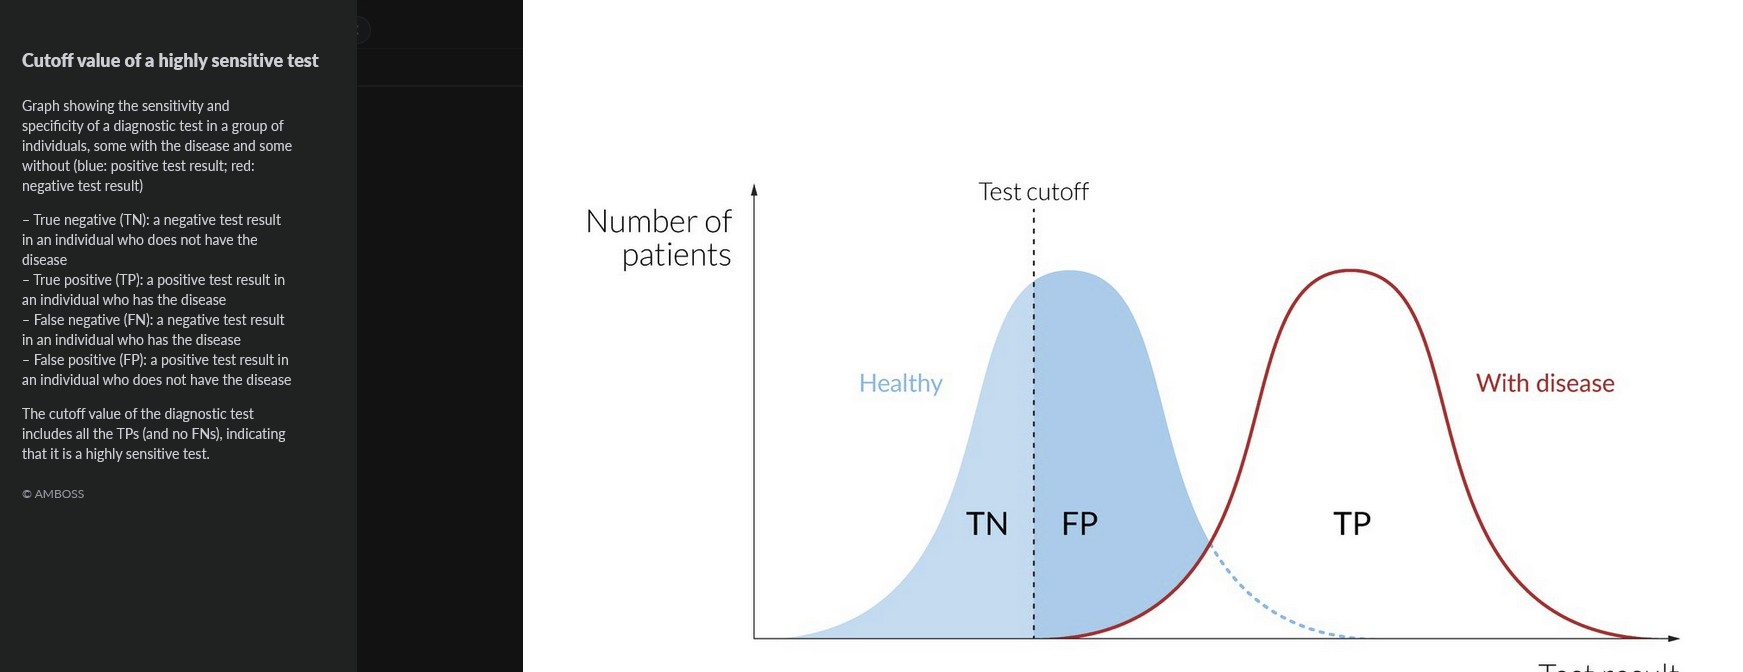

sensitivity =

proportion of individuals with disease for which the test was positive

TP/(TP+FN)

rules OUT disease, best for screening

specificity =

proportion of individuals without the disease with a negative test

TN/(TV+FP)

CONFIRMS disease, best used after a high-sensitivity screening test

1 - sensitivity =

false negative rate

1 - specificity =

false positive rate